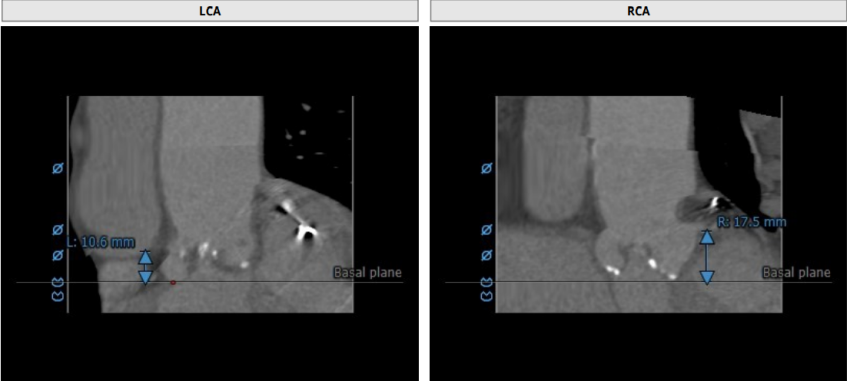

术前CT评估

瓣环:23.4mm LVOT:24.6mm

左冠高度:10.6mm 右冠高度:17.5mm